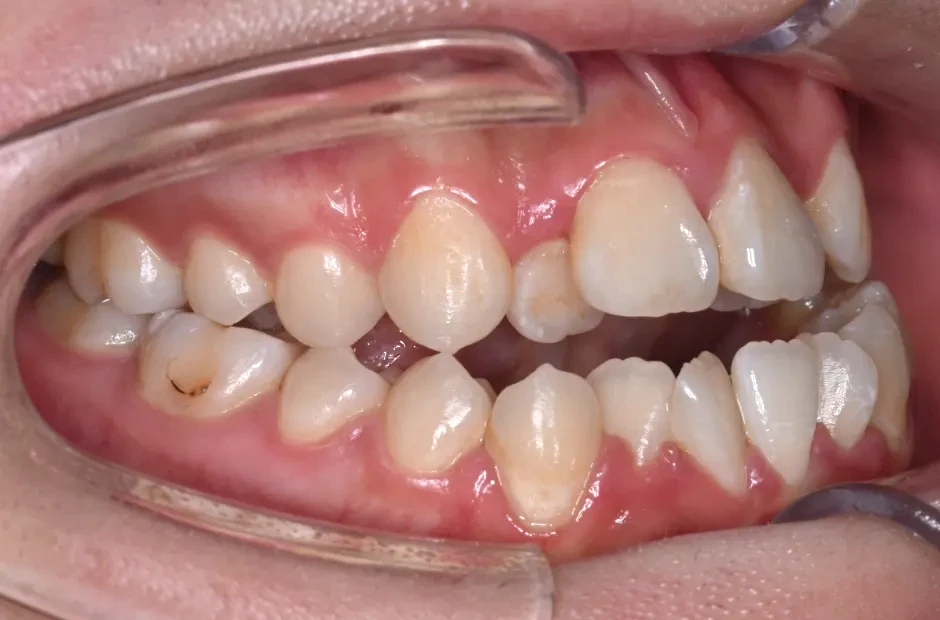

叢生

| 診断名・主訴 | 叢生 |

|---|---|

| 年齢・性別 | 43歳・女性 |

| 治療期間・回数 | 2年7か月 27回 |

| 治療に用いた主な装置 | 舌側矯正 |

| 抜歯部位 | 両顎4,4 |

| 治療費 | 100万円(税抜) |

| リスク・副作用 | 装置による違和感・疼痛・歯肉退縮・歯根吸収・虫歯のリスクなど |

治療前